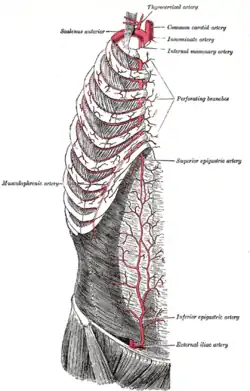

Right internal thoracic artery and its branches (labeled under its old name the Internal mammary artery, at upper right). | |

| Branches | Pericardiocophrenic Anterior intercostal branches Musculophrenic Superior epigastric Perforating branches |

In human anatomy, the internal thoracic artery (ITA), also known as the internal mammary artery, is an artery that supplies the anterior chest wall and the breasts.[1] It is a paired artery, with one running along each side of the sternum, to continue after its bifurcation as the superior epigastric and musculophrenic arteries.

The internal thoracic artery arises from the anterior surface of the subclavian artery near its origin.[2][3] It has a width of between 1-2 mm.[4]

It travels downward on the inside of the rib cage, approximately 1 cm from the sides of the sternum,[3] and thus medial to the nipple. It is accompanied by the internal thoracic vein.

Branches

- Mediastinal branches

- Thymic branches

- Pericardiacophrenic artery - travels with the phrenic nerve

- Sternal branches

- Perforating branches

- Twelve anterior intercostal branches, two to each of the top six intercostal spaces. In a given space, the upper branch travels laterally along the bottom of the rib until it anastomoses with its corresponding posterior intercostal artery. The lower branch of the space anastomoses with a collateral branch of the posterior intercostal artery.

After passing the sixth intercostal space, the internal thoracic artery splits into the following two terminal branches:

- Musculophrenic artery - roughly follows the costal margin and it again gives branch for 7,8,9 ribs

- Superior epigastric artery - continues the course of the internal thoracic artery, travelling downward into the abdominal wall and to the content of rectus sheath